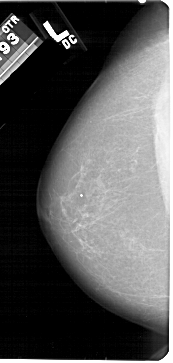

A_1428_1.RIGHT_MLO

RIGHT_MLO LINES 5491 PIXELS_PER_LINE 2836 BITS_PER_PIXEL 12 RESOLUTION 43.5 OVERLAY